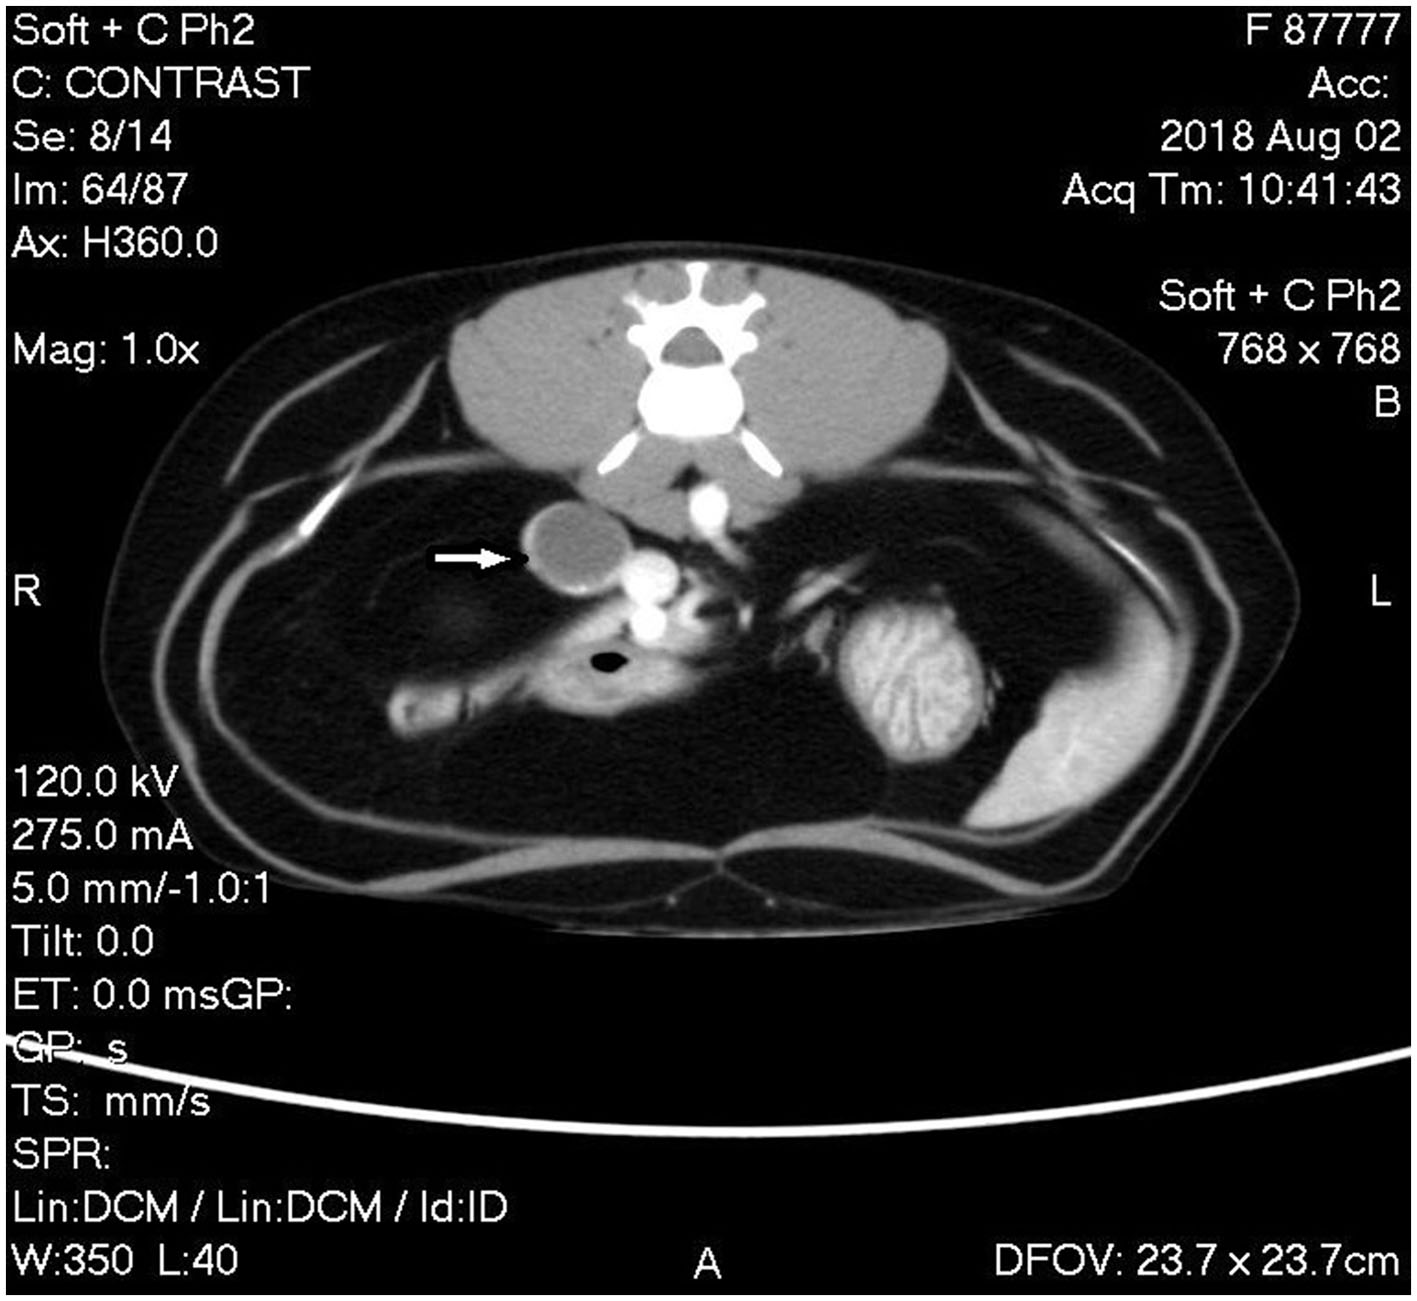

A triple phase-contrast abdominal computed tomography (CT) was performed to fully assess the adrenal mass and thoracic CT for metastasis evaluation. The cranial pole of the right adrenal was markedly enlarged at 1.8 cm diameter × 3.4 cm craniocaudal length with a hypoattenuating nodule in the caudal pole measuring 1.8 cm in diameter. The nodule had marked rim enhancement and mild homogenous central enhancement in the arterial and venous phases. The right phrenicoabdominal vein was in close apposition to the caudal aspect of the adrenal nodule and the right adrenal gland was in close apposition to the caudal vena cava without visible flattening or filling defects (Figure 2). The left adrenal gland was noted to be within normal limits at 0.6 cm dorsoventral diameter. There were multiple hypoattenuating splenic nodules, consistent with myelolipoma characteristics in the spleen of domestic cats.

Figure 2. Computed tomography (CT) image of phase 2 post-contrast study of the abdomen showing the mass associated with the caudal pole of the right adrenal gland with rim enhancement and mild homogenous central enhancement (white arrow).

The CT findings were consistent with a right adrenal mass without invasion into the caudal vena cava or renal vasculature. Differential diagnoses included possible neoplastic processes, such as adrenocortical adenoma and carcinoma or pheochromocytoma, although nodular hyperplasia could not be ruled out. Surgical exploration and right adrenal resection were recommended for excisional biopsy to determine the diagnosis.